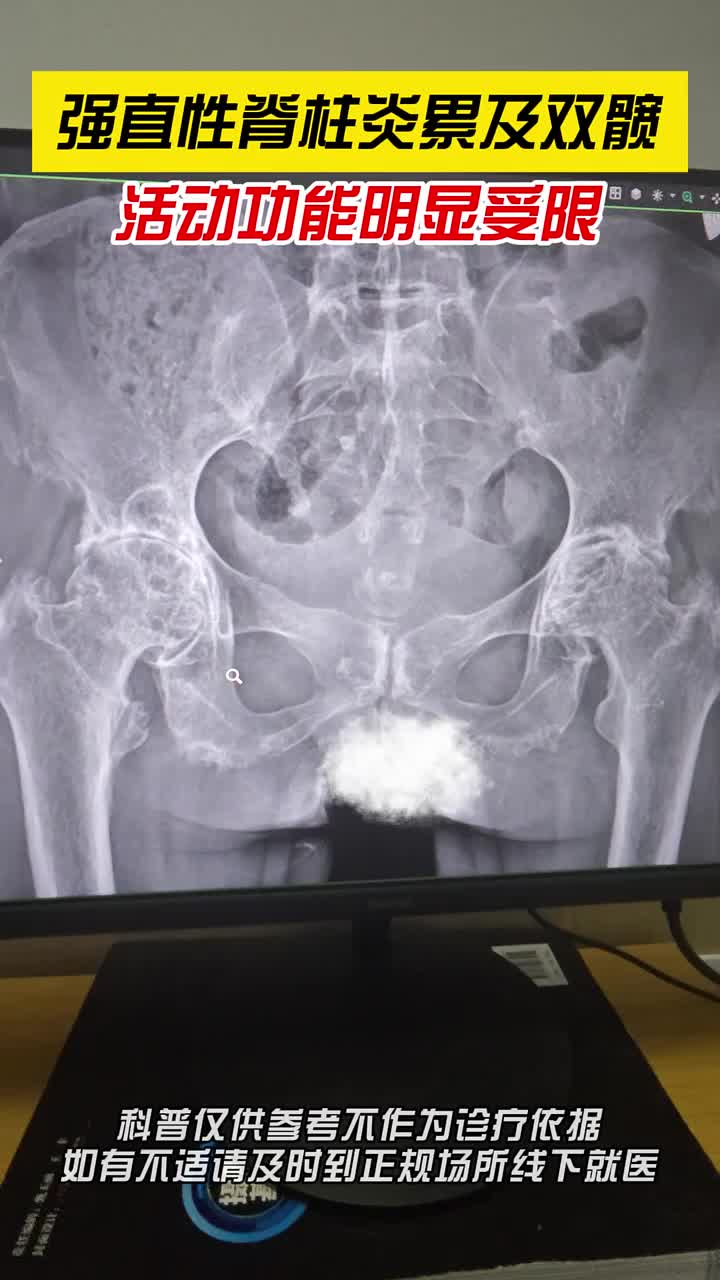

强直性脊柱炎累及双髋,活动受限!

图片尺寸720x1280